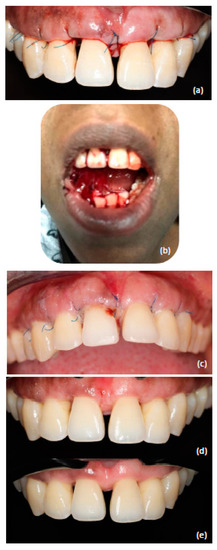

- PSI: Accessing flap 13–23 with a combination of buccal papilla preservation at 11–21 and osteoplasty where needed (Figure 2d–f); procedure is a combination of the modified papilla preservation technique as described by Cortellini and Tonetti [30] and open flap debridement as described by Carranza and Takei [31].